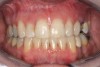

Fig 2 (and Fig 3). Corticotomy SFOT. The patient presented with unesthetic anterior bridgework that was placed at age 14 to compensate for congenitally missing Nos. 7 and 10.

Figure 2

Fig 3 (and Fig 2). Corticotomy SFOT. The patient presented with unesthetic anterior bridgework that was placed at age 14 to compensate for congenitally missing Nos. 7 and 10.

Figure 3